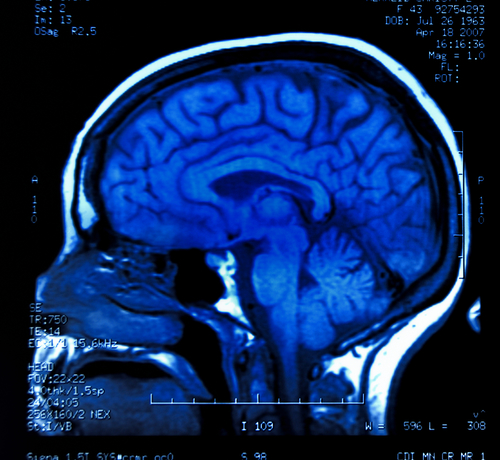

The researchers, led by Kent Kiehl, performed a functional MRI scan on the male prisoners at the time of their release, looking specifically at the anterior cingulate cortex, an area at the front of the brain that is involved in decision making. They were required to quickly decide whether they were seeing an X or a K on a computer screen.